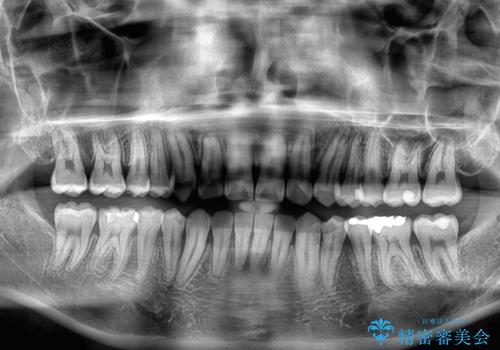

1年強でワイヤー装置を外すことができ、思ったよりも短期間で終了したため、患者様には大変喜んでいただきました。